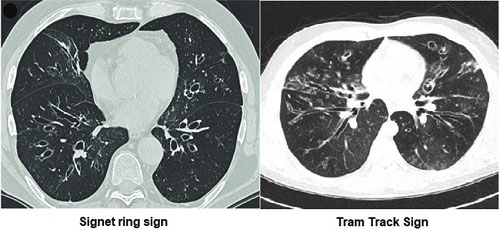

• เอกซเรย์คอมพิวเตอร์ความละเอียดสูง (HRCT) เป็นมาตรฐานในการวินิจฉัย พบหลอดลมขยายใหญ่กว่าหลอดเลือดคู่กัน (signet-ring sign) ผนังหนา ลักษณะ “รางรถไฟ” (tram-track) หรือการแตกแขนงผิดปกติ

3. หลักฐานจาก HRCT พบหลอดลมขยายถาวร

COPD (โดยเฉพาะ chronic bronchitis) ไอเรื้อรัง มีเสมหะ ประวัติสูบบุหรี่ สมรรถภาพปอดแบบอุดกั้น HRCT ไม่มีการขยายหลอดลมแบบ signet-ring sign; มักตอบสนองต่อยาขยายหลอดลมมากกว่า